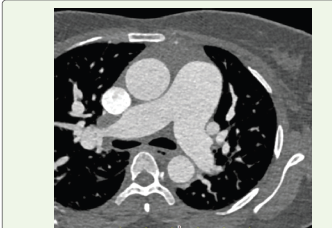

Figure 4:Axial contrast-enhanced CT image at the level of the pulmonary

artery bifurcation demonstrating dilatation of the main pulmonary artery,

suggestive of pulmonary hypertension.

vena cava enlargement, and pulmonary arterial dilatation were

evident on CT, reflecting significant hemodynamic impact.

communication.The aneurysmal sac was noted to protrude into the right atrium, producing indentation of the adjacent tricuspid valve leaflet. There was significant dilatation of the right atrium and inferior vena cava, with associated hepatic venous congestion. The main pulmonary artery was dilated, measuring approximately 3.9 cm, suggestive of pulmonary hypertension. Mild pericardial effusion and cardiomegaly were also present.